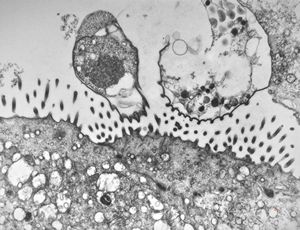

F,52y. | spirochetosis - colon

F,52y. | colon … spirochetosis … subepitheliai microbes